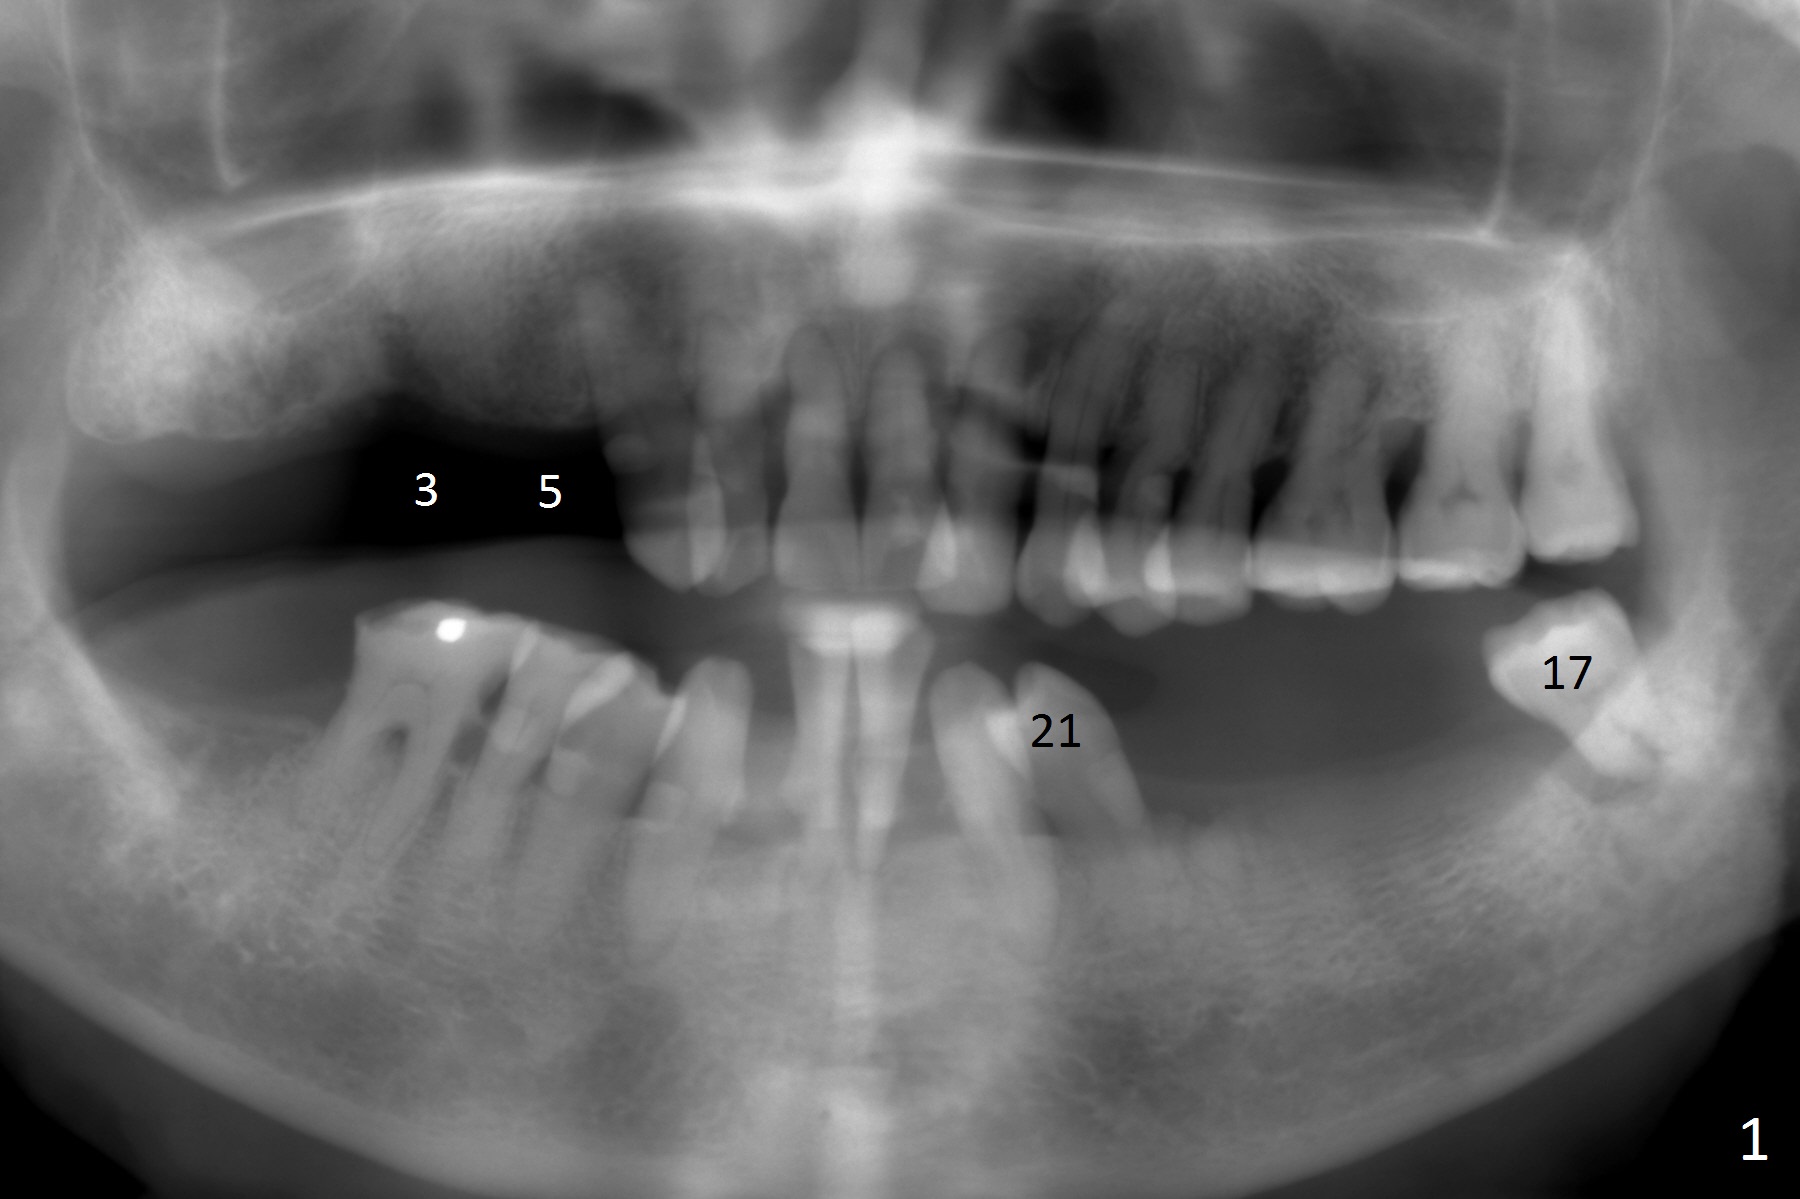

A 83-year-old woman requests lower RPD to replace #18-20 and 23-26 (Fig.1), although UR FPD supported by implants at #3 and 5 (Fig.2,3) is a better option.  For the RPD, an implant will be placed at #18 (Fig.4) or 17 (Fig.5) with ball abutment.  At #18, a shorter implant will be placed at the top of the Inferior Alveolar Canal (brown), while at #17, a longer implant will be placed buccal (B) to the canal.